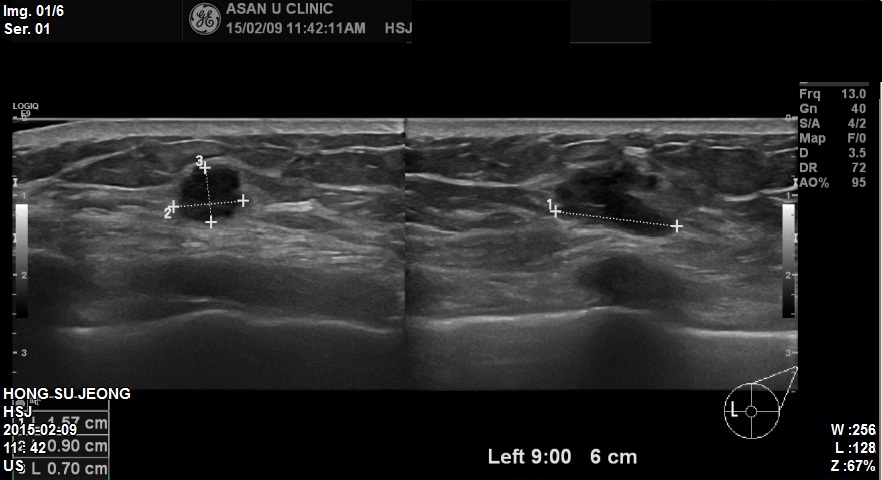

본원내원하신 60대 환자분이십니다.

좌측유방 9시방향에 1.6cm 혹 조직검사 시행하였고

침윤성유관암 진단되었습니다. 감사합니다.